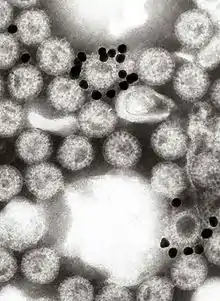

The virus is transmitted by the faecal–oral route. It infects and damages the cells that line the small intestine and causes gastroenteritis (which is often called "stomach flu" despite having no relation to influenza). Although rotavirus was discovered in 1973 by Ruth Bishop and her colleagues by electron micrograph images[5] and accounts for approximately one third of hospitalisations for severe diarrhoea in infants and children,[6] its importance has historically been underestimated within the public health community, particularly in developing countries.[7] In addition to its impact on human health, rotavirus also infects other animals, and is a pathogen of livestock.[8]

In 1974, Thomas Henry Flewett suggested the name rotavirus after observing that, when viewed through an electron microscope, a rotavirus particle looks like a wheel (rota in Latin)[154][155] the name was officially recognised by the International Committee on Taxonomy of Viruses four years later.[156] In 1976, related viruses were described in several other species of animals.[153] These viruses, all causing acute gastroenteritis, were recognised as a collective pathogen affecting humans and other animals worldwide.[154] Rotavirus serotypes were first described in 1980,[157] and in the following year, rotaviruses from humans were first grown in cell cultures derived from monkey kidneys, by adding trypsin (an enzyme found in the duodenum of mammals and now known to be essential for rotavirus to replicate) to the culture medium.[158] The ability to grow rotaviruses in culture accelerated the pace of research, and by the mid-1980s the first candidate vaccines were being evaluated.[159]